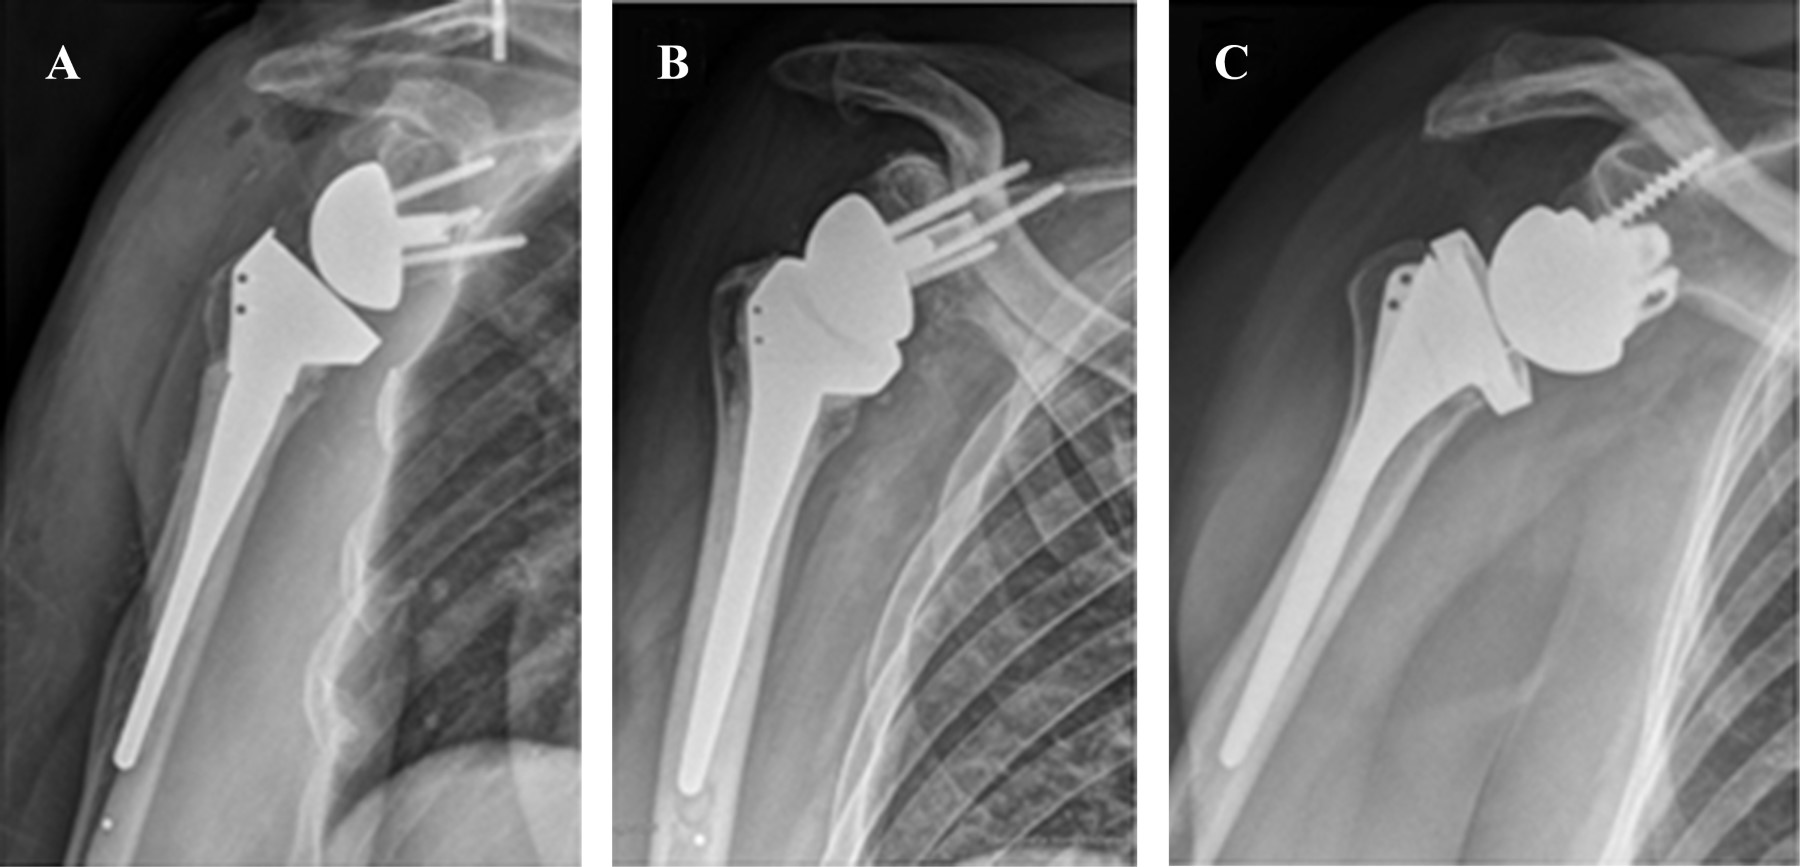

Purpose: Compare functional and radiological outcomes of three different designs of reverse shoulder arthroplasty according to distalization and lateralization shoulder angle, in heterogenic diagnostics (fracture, cuff arthropathy, fracture sequela and osteoarthritis). Material and methods: Prospective cohort of 33 patients of reverse shoulder arthroplasty (RSA) between December 2014 and July 2017 with a minimum one year of follow-up. We defined three groups, G: 10 patients with Grammont (155o, Medialized Glena), B: 9 patients with Bio-RSA (155º, lateralized bone glena) and A: 14 patients with Arrow (135o, lateralized metallic glena). We analyze demographic, clinical, functional and radiological outcomes (lateralization shoulder angle (LSA) and distalization shoulder angle (DSA)). For the statistical analysis, ANOVA, T-tests and linear regression tests were used, with a statistical significance of 5%. Results: The LSA was significantly higher in group A (98o A, 79o G, 80o B) (p < 0.05). In DSA, group B was significantly higher than A (52o B, 39o A) (p < 0.05) and not significant to G (48o G) (p = 0.06). There was no correlation of LSA and DSA with external rotation (p = 0.51) and active elevation (p = 0.41), respectively. There was no significant clinical (anterior elevation, external rotation, internal rotation) and functional outcomes (adjusted Constant score and subjective shoulder evaluation) differences between the different RSA models (p > 0.05). Conclusions: The LSA was higher in the Arrow and the DSA was higher in Bio-RSA. We did not find Clinical - Radiological correlation in this heterogeneous series of patients.

Figure 2